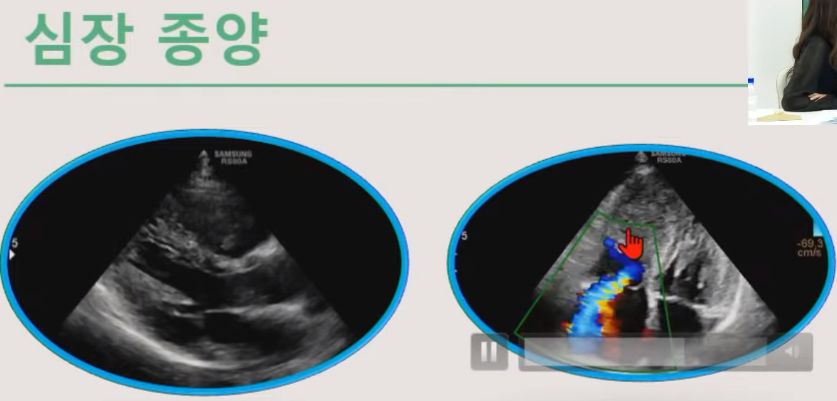

ㅡ 심장초음파검사로 심장크기, (심장벽)두께 측정, 심장기능 평가, 판막질환 진단 및 평가, 선천성 심장질환 진단, 심낭 삼출, 심장종양 진단.

ㅡ 심장초음파로 심장의 구조와 기능 평가. 도플러 초음파를 이용해 혈역학적 평가 가능. 심장질환의 진단, 치료방침, 예후 판정.

심장 종양, 심낭 삼출

ㅡ 심장초음파 검사는 심장의 구조와 기능을 평가.

ㅡ 도플러 초음파를 이용하여 혈역학적 평가 가능.

* 실제 영상을 보세요. 각 경우를 동영상으로 보여줍니다.